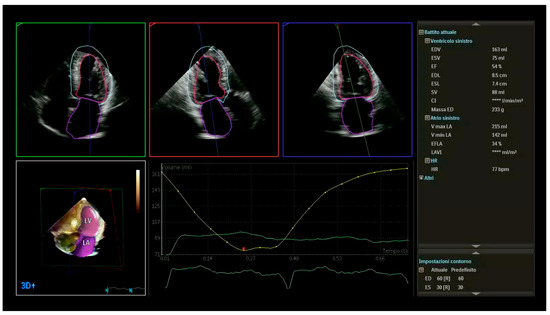

- Tsang, W.; Salgo, I.S.; Medvedofsky, D.; Takeuchi, M.; Prater, D.; Weinert, L.; Yamat, M.; Mor-Avi, V.; Patel, A.R.; Lang, R.M. Transthoracic 3D Echocardiographic Left Heart Chamber Quantification Using an Automated Adaptive Analytics Algorithm. JACC Cardiovasc. Imaging 2016, 9, 769–782. [Google Scholar] [CrossRef]

- Volpato, V.; Mor-Avi, V.; Narang, A.; Prater, D.; Gonçalves, A.; Tamborini, G.; Fusini, L.; Pepi, M.; Patel, A.R.; Lang, R.M. Automated, machine learning-based, 3D echocardiographic quantification of left ventricular mass. Echocardiography 2019, 36, 312–319. [Google Scholar] [CrossRef]

- Italiano, G.; Tamborini, G.; Fusini, L.; Mantegazza, V.; Doldi, M.; Celeste, F.; Gripari, P.; Muratori, M.; Lang, R.M.; Pepi, M. Feasibility and Accuracy of the Automated Software for Dynamic Quantification of Left Ventricular and Atrial Volumes and Function in a Large Unselected Population. J Clin. Med. 2021, 10, 5030. [Google Scholar] [CrossRef]